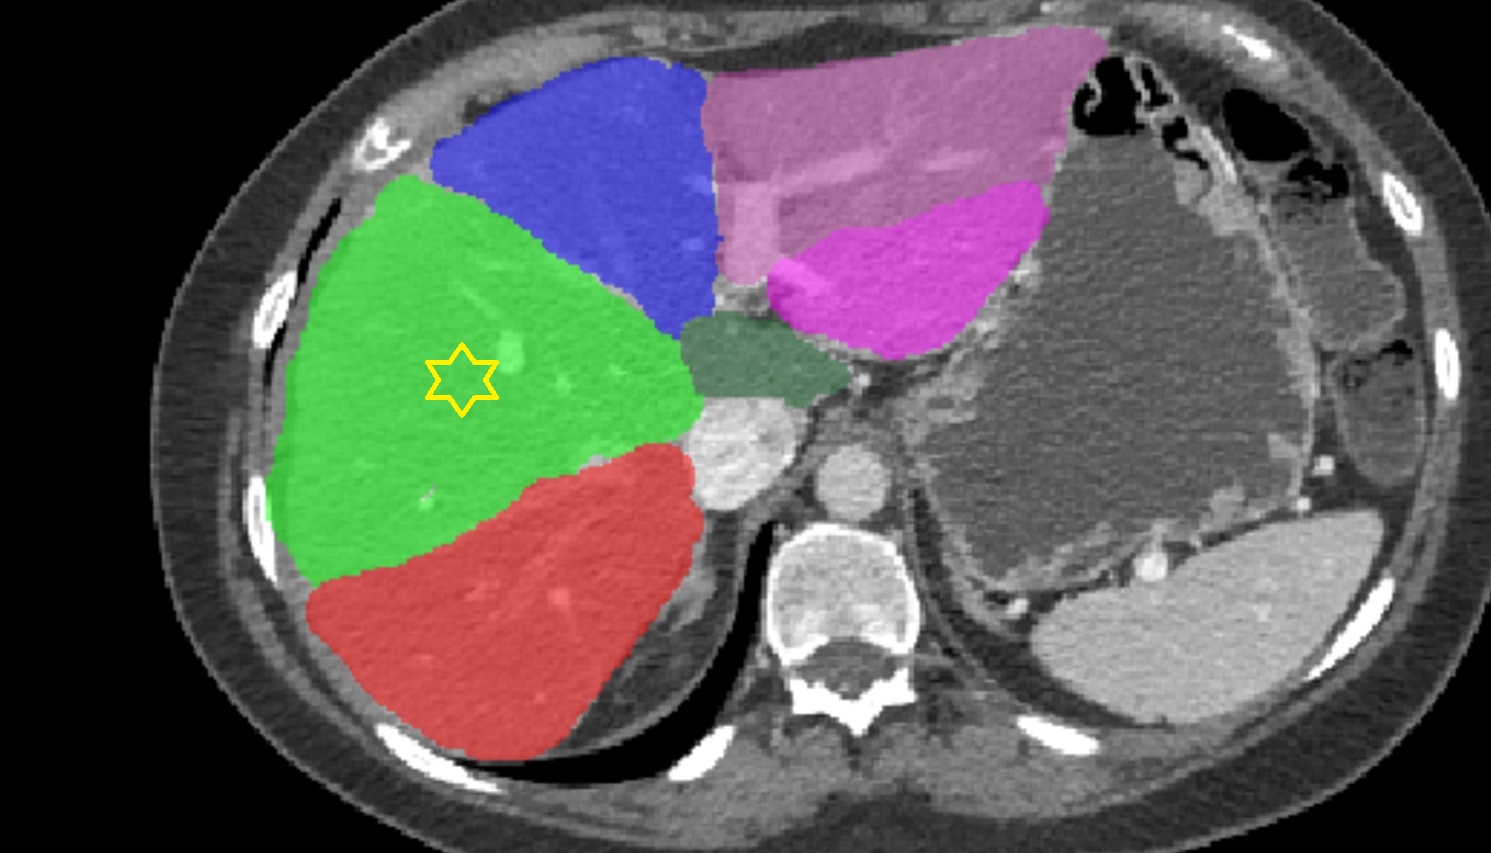

CT image

Liver Right anterosuperior segment — Segment VIII   CT  axial  anatomy  image